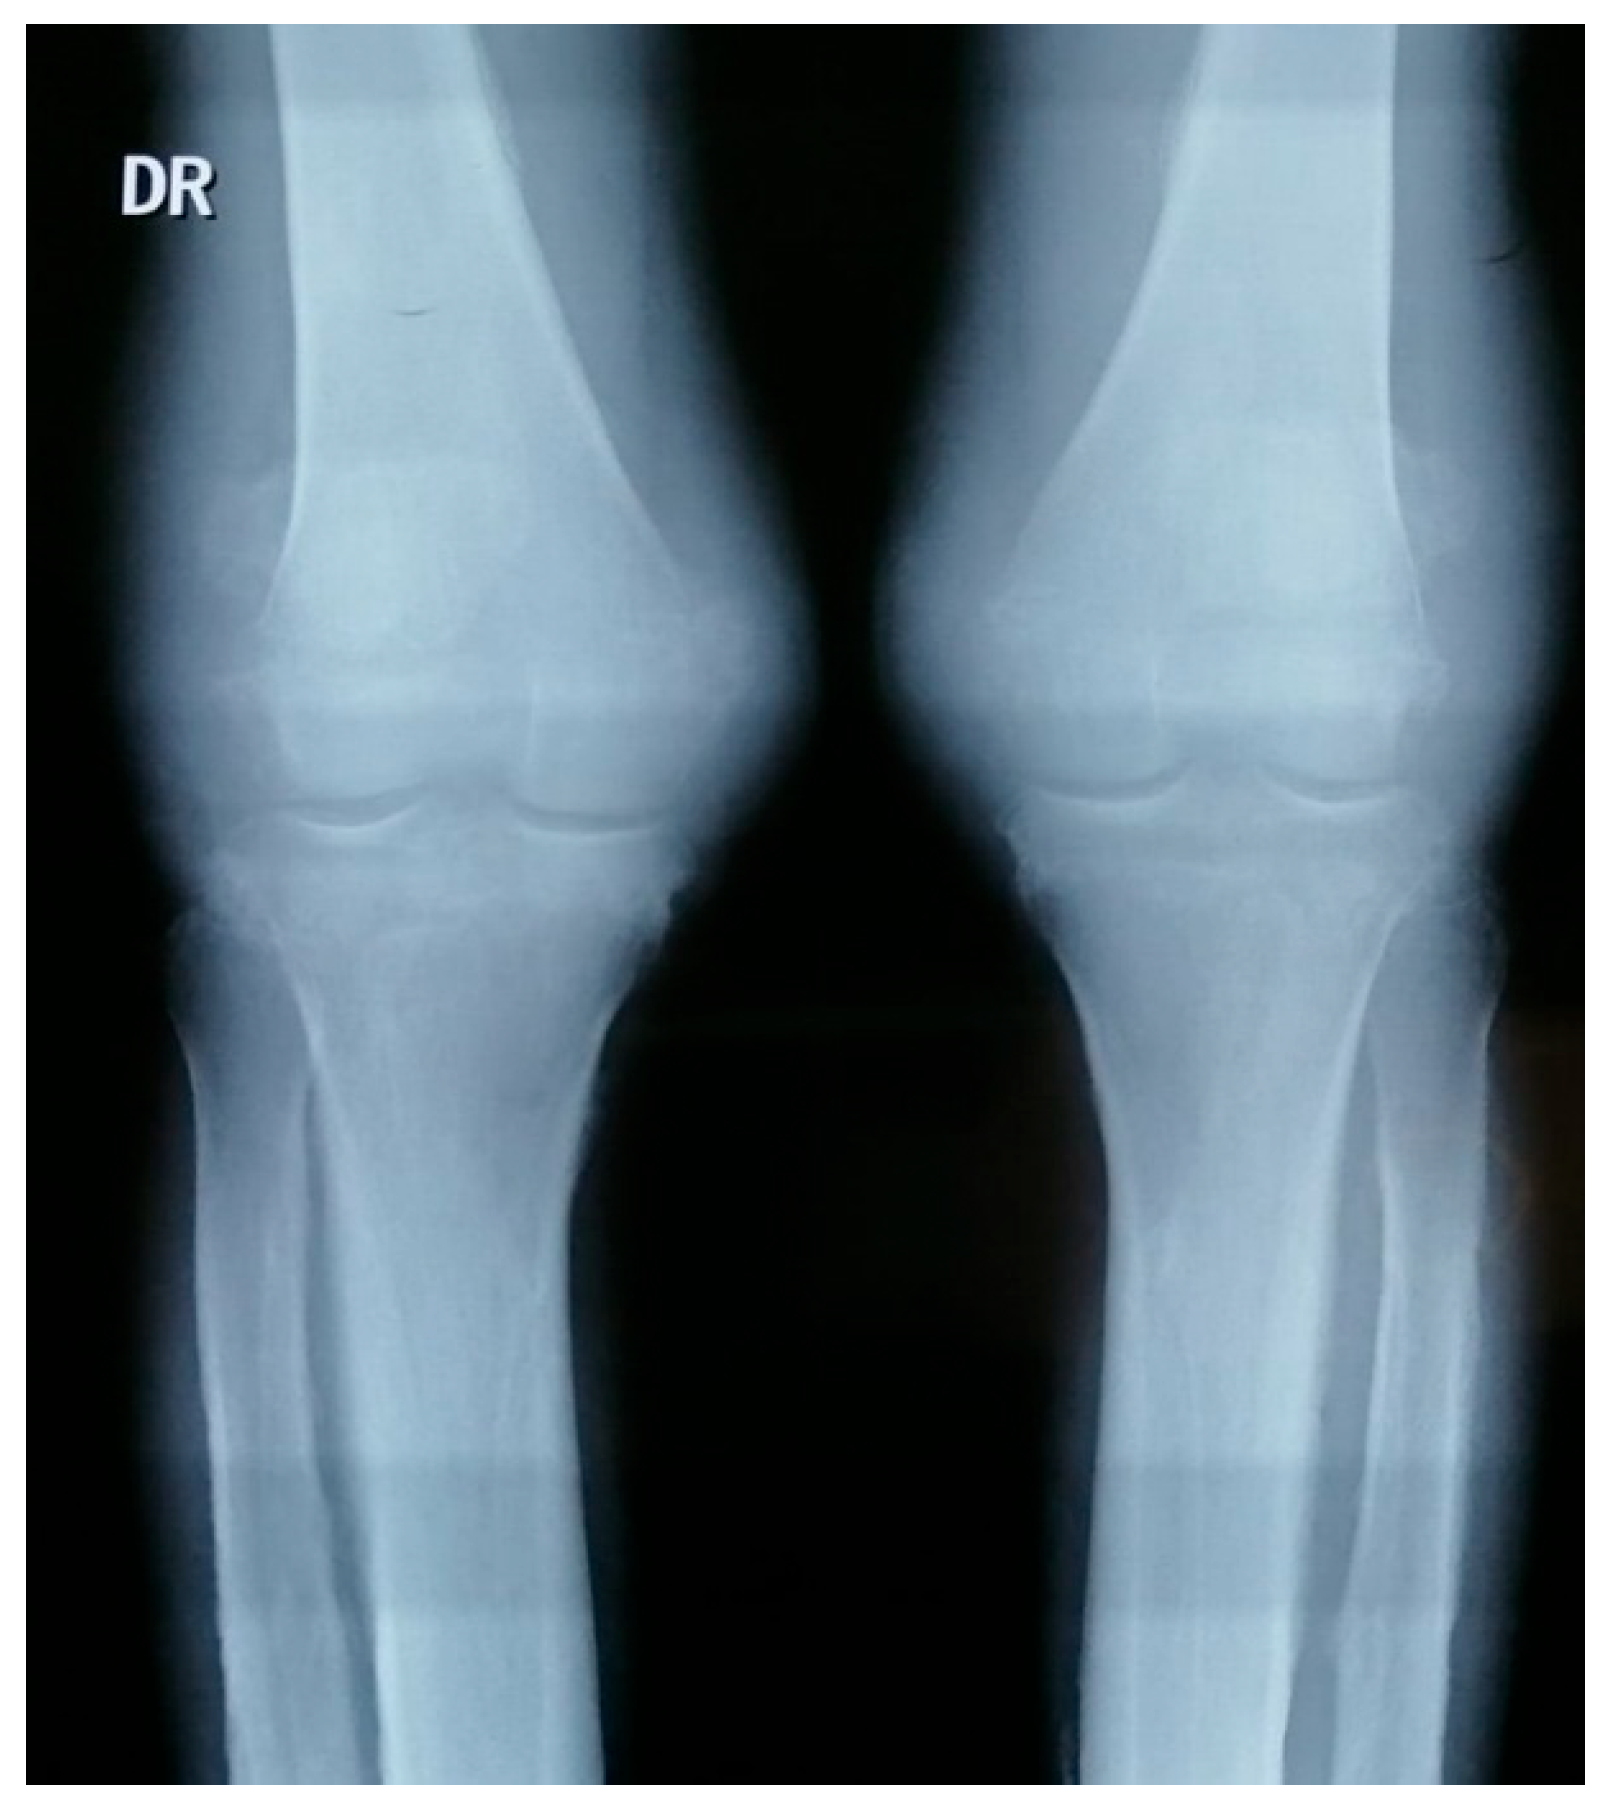

- Knee X-rays: periosteal reaction involving tibia, fibula and femur (Figure 4).